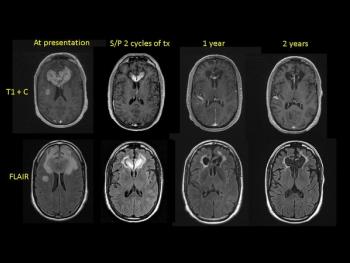

Primary central nervous system lymphoma (PCNSL) is a rare but aggressive malignancy that accounts for approximately 3% of all primary CNS cancer. New studies have changed the landscape of PCNSL treatment paradigms and expectations for outcome.